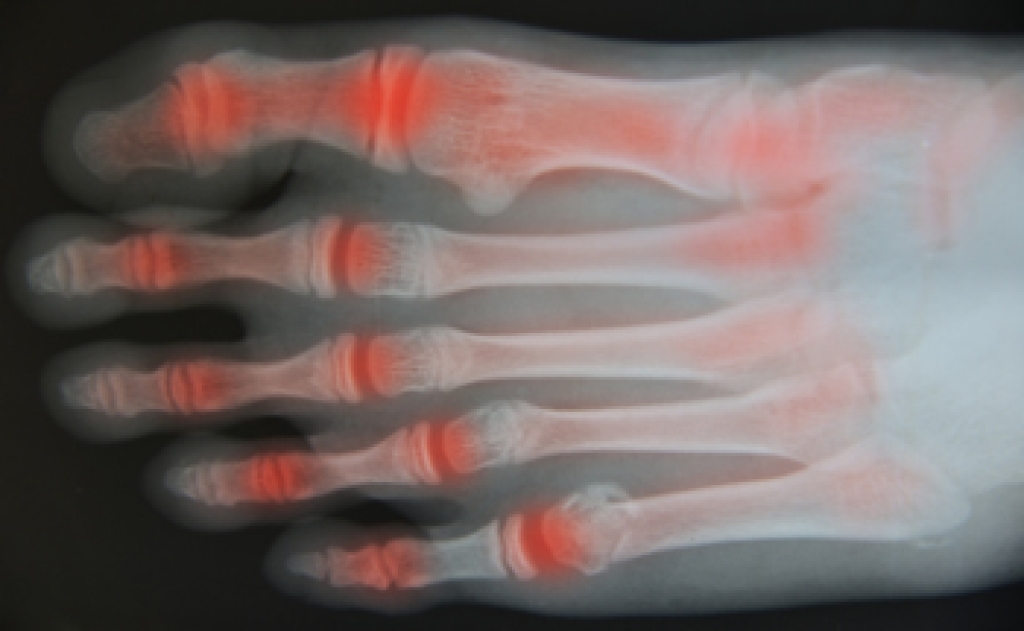

Diagnosis of cuboid syndrome is often difficult, and it is often misdiagnosed. X-rays, MRIs and CT scans often fail to properly show the cuboid subluxation. Although there isn’t a specific test used to diagnose cuboid syndrome, your podiatrist will usually check if pain is felt while pressing firmly on the cuboid bone of your foot.